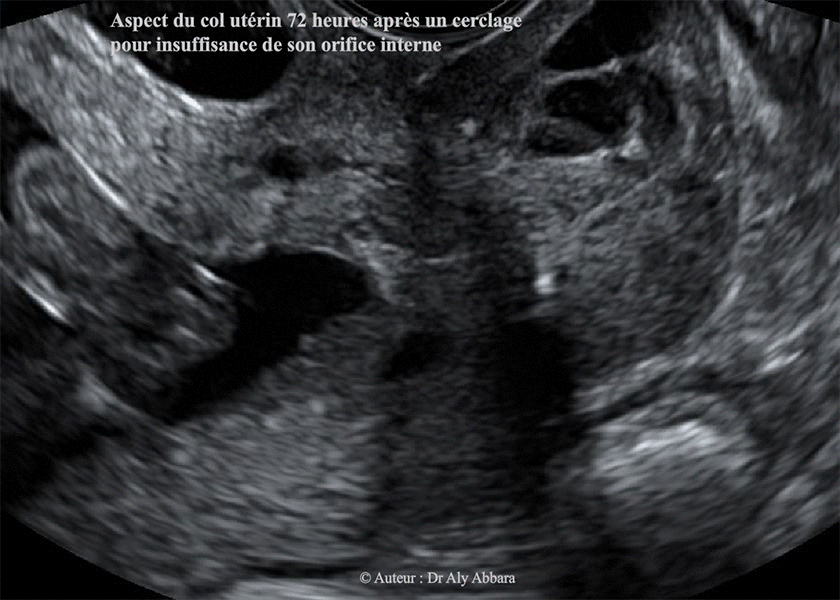

Même col utérin après cerclage

Incompétence de l'orifice interne du col utérin - Sévère menace d'avortement tardive à 18 SA - Aspect échographique du col utérin après un cerclage

Le cerclage du col utérin à chaud a permis d'obtenir une fermeture totale du canal cervical sur une longueur de 27 mm (longueur à fermeture efficace mesurée à l'échographie post-cerclage).